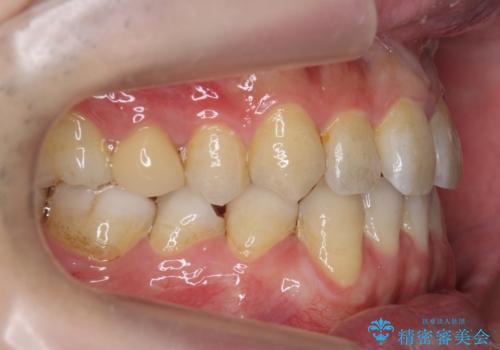

前歯の矮小歯 奥歯の反対咬合 をインビザラインで

- 上下の前歯が気になり来院。

左上2が矮小歯で小さく、また、左の奥歯が反対咬合になっていました。

左上2番はセラミッククラウンで反対側と同じ大きさにしました。

インビザラインでの臼歯の反対咬合の治療は難しいことが多いです。

今回は下の前歯を1本抜くことで、下の奥歯をしっかり内側に傾けて治療を行いました。